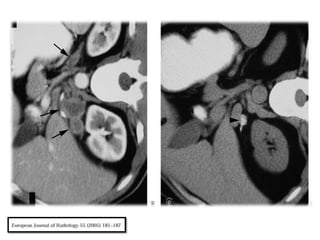

Próstata

La Tuberculosis de la próstata suele ser secundaria a la

infección del tracto urinario superior.

Necrosis, calcificación, necrosis caseosa son las

manifestaciones patológicas comúnmente

encontradas.

Sin embargo, cuando no hay calcificación, la infección

prostática no se pueden distinguir de los abscesos

piógenos.

Además, el antígeno prostático específico (PSA) puede

ser elevada en aproximadamente el tercio de los

pacientes .

Sin antecedentes de afectación de otros órganos por

tuberculosis, el diagnóstico generalmente se obtiene

después de la biopsia.